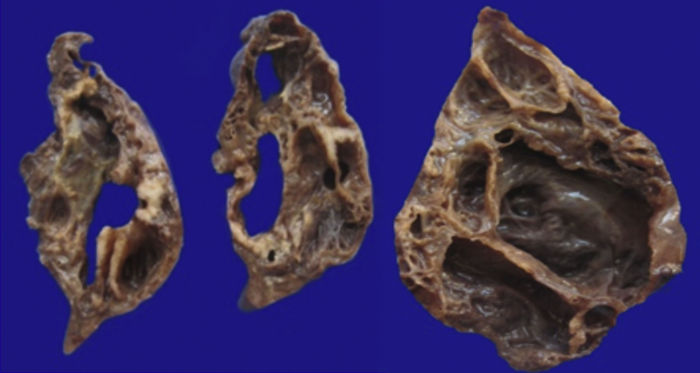

Además del producto de la lobectomía superior izquierda, también se recibió la placenta, que pesó 700 g y midió 21 × 20 cm. Las membranas estaban íntegras. Por la cara materna se pudieron observar los cotiledones sin alteración y por la cara fetal las membranas congestivas con inserción central del cordón. Era una placenta monoamniótica, monocoriónica (Figura 5). Los diferentes cortes de la placenta mostraron el cordón con vasos sanguíneos sin alteraciones, las membranas íntegras y congestivas, y la placenta con vellosidades del tercer trimestre del embarazo, con presencia de algunos trombos hialinizados y calcificaciones propias de la edad gestacional (Figura 6).